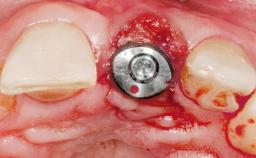

Late Placement of an Implant in a Maxillary Left Central Incisor Site

# of Implants 1

Type of Implants Two-Piece

Placement Protocol Early or late implant placement